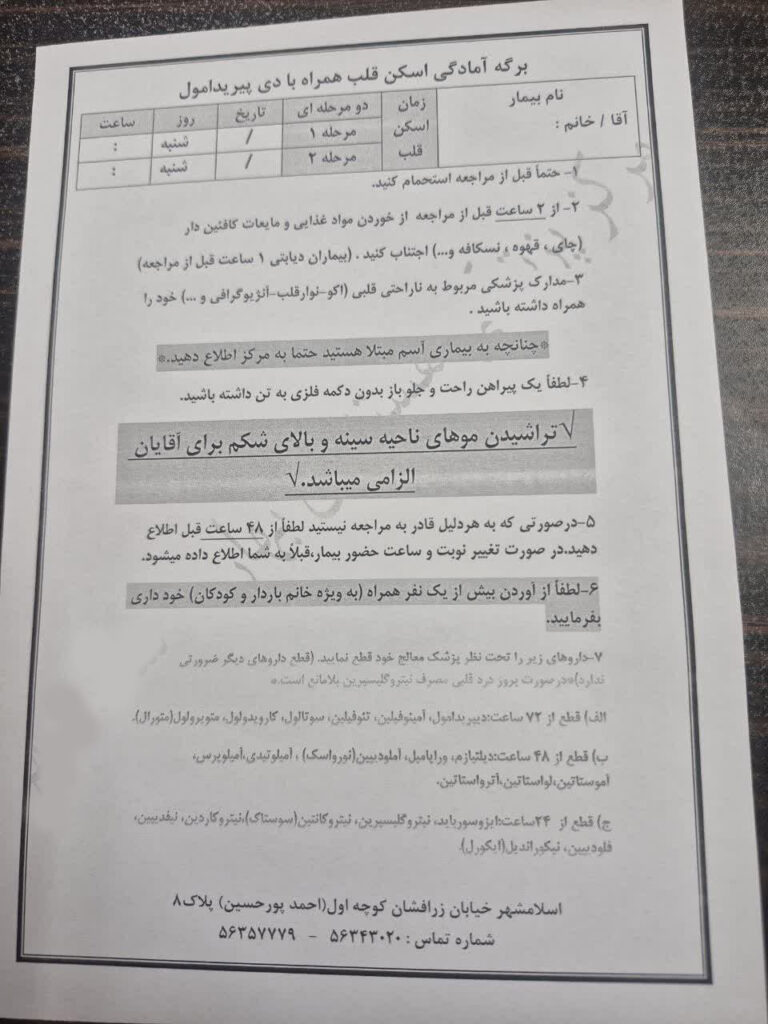

فرمهای زیر مربوط به مراحل آمادگی بیماران پیش از انجام اسکن قلب هستند.پیش از انجام اسکن قلب، لازم است فرمهای زیر را بهمنظور آمادهسازی و بررسی اولیه تکمیل کنید.

۴. آمادگیهای قبل از اسکن (مانند قطع برخی داروها یا ناشتا بودن) را دقیقاً طبق دستور مرکز انجام دهید تا نیاز به تکرار آزمایش و اتلاف وقت بیشتر نباشد.